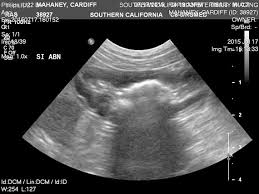

Signs Of Intestinal Cancer Dogs : Canine Lymphoma Ethos Veterinary Health - Generally, a dog with intestinal cancer exhibits common symptoms such as anorexia, vomiting, bloody diarrhea, weight loss, abdominal pain and tremors, ascites (fluid accumulation in the abdomen) and in some cases severe constipation.. If the tumor is large enough to cause a blockage, your dog becomes severely constipated. Other signs of canine abdominal cancer include anemia, lethargy, diarrhea, bloody stool, dark colored stool, loss of appetite, and loss of sleep. Vomiting tends to occur more with tumors in the upper (small) intestine while diarrhea is more common with tumors of the lower (large) intestine. Dogs are naturally curious, and many have a desire to eat or chew almost anything. Symptoms symptoms associated with canine intestinal cancer and stomach cancer include:

Digestive Tract Intestinal Epithelial Tumors Vca Animal Hospital from vcahospitals.com Generally, a dog with intestinal cancer exhibits common symptoms such as anorexia, vomiting, bloody diarrhea, weight loss, abdominal pain and tremors, ascites (fluid accumulation in the abdomen) and in some cases severe constipation. These are common forms of cancer in dogs, especially in the mouth. Here are some of the most common signs of cancer in dogs and the types of cancer that cause them. Some of the symptoms of intestinal tumors, including adenocarcinomas, are: Diarrhea, constipation, and vomiting also show anything will go incorrect with your pet's digestive tract. Vomiting (with or without blood) Belgian shepherds have an increased risk for stomach. Blood in the feces, or tarry, dark stools, could indicate the tumor is bleeding.

The usual clinical signs of intestinal cancer are weight loss, loss of appetite, vomiting, diarrhea and blood in vomit or feces. Sometimes these masses will ulcerate and bleed. It can become fatal if the tumor is situated near the small or large intestine, since it can restrict the passage of bowel and pose health hazards. While the stomach tumors might be fought successfully, most stomach cancers quickly spread to the lymph nodes and other organs. If your dog seems to be going to the bathroom more often or having trouble with it, get him checked out.